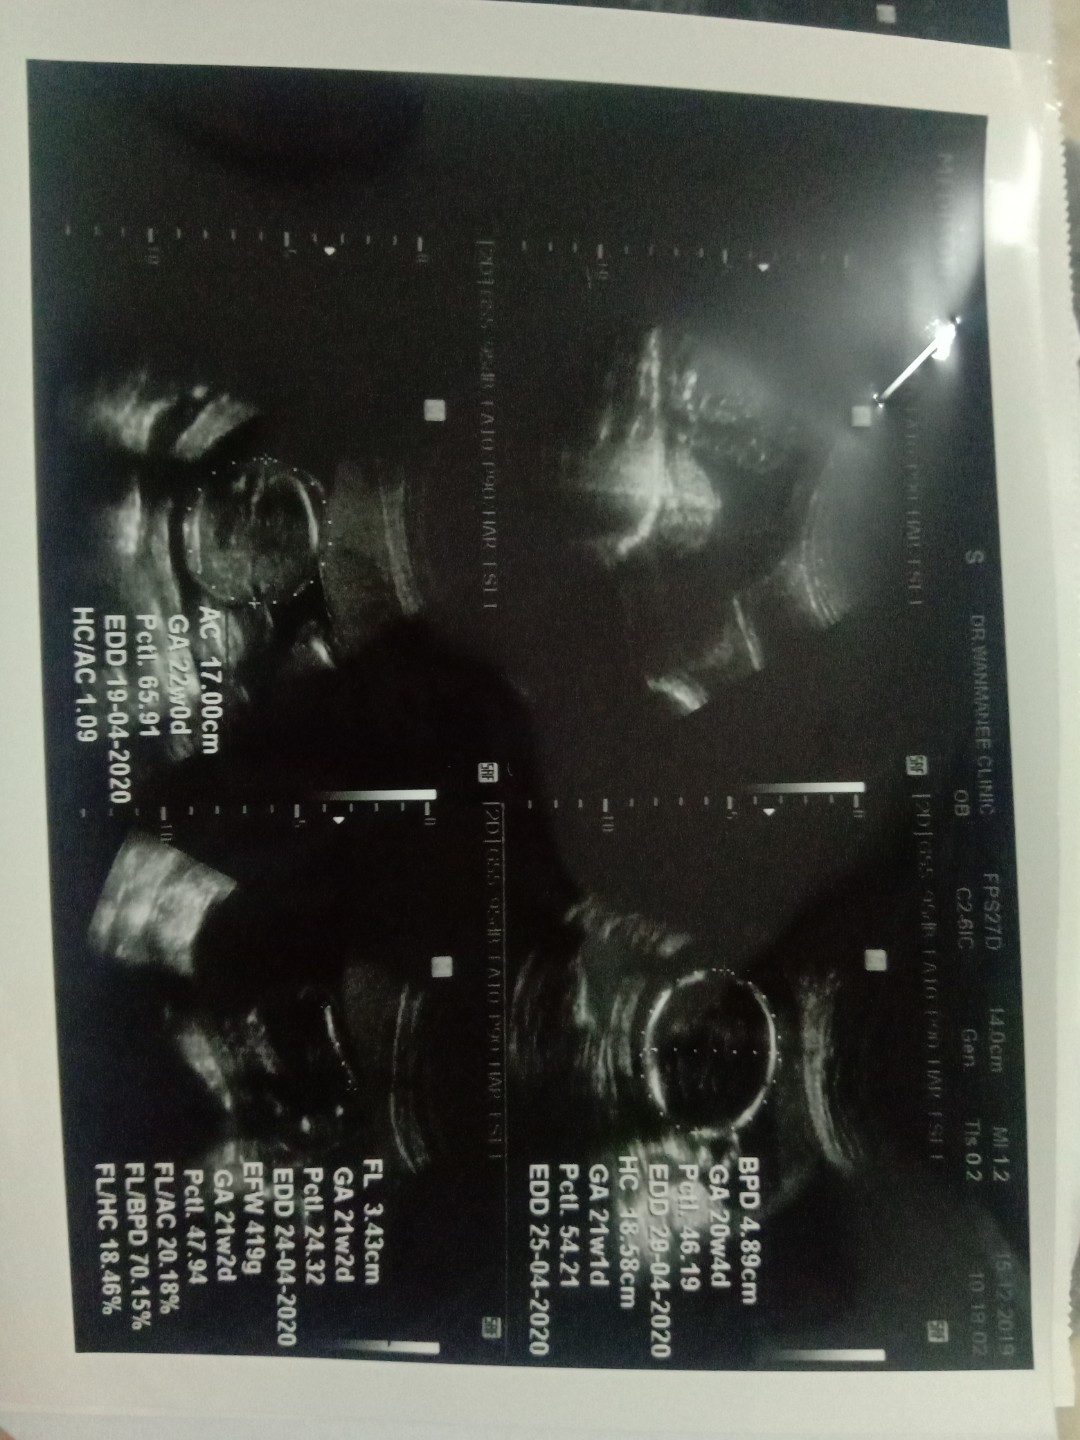

แม่ๆคนไหนกำหนดคลอดเมษาบ้างคะ ได้ชายหรือหญิง บ้านนี้ได้ผู้หญิงจ้า #21week สมกับที่รอคอย ?

23+1W คลอด15เมษาได้ผู้หญิงจ้า

24เมษาจ้า แฝดหญิงจ้า